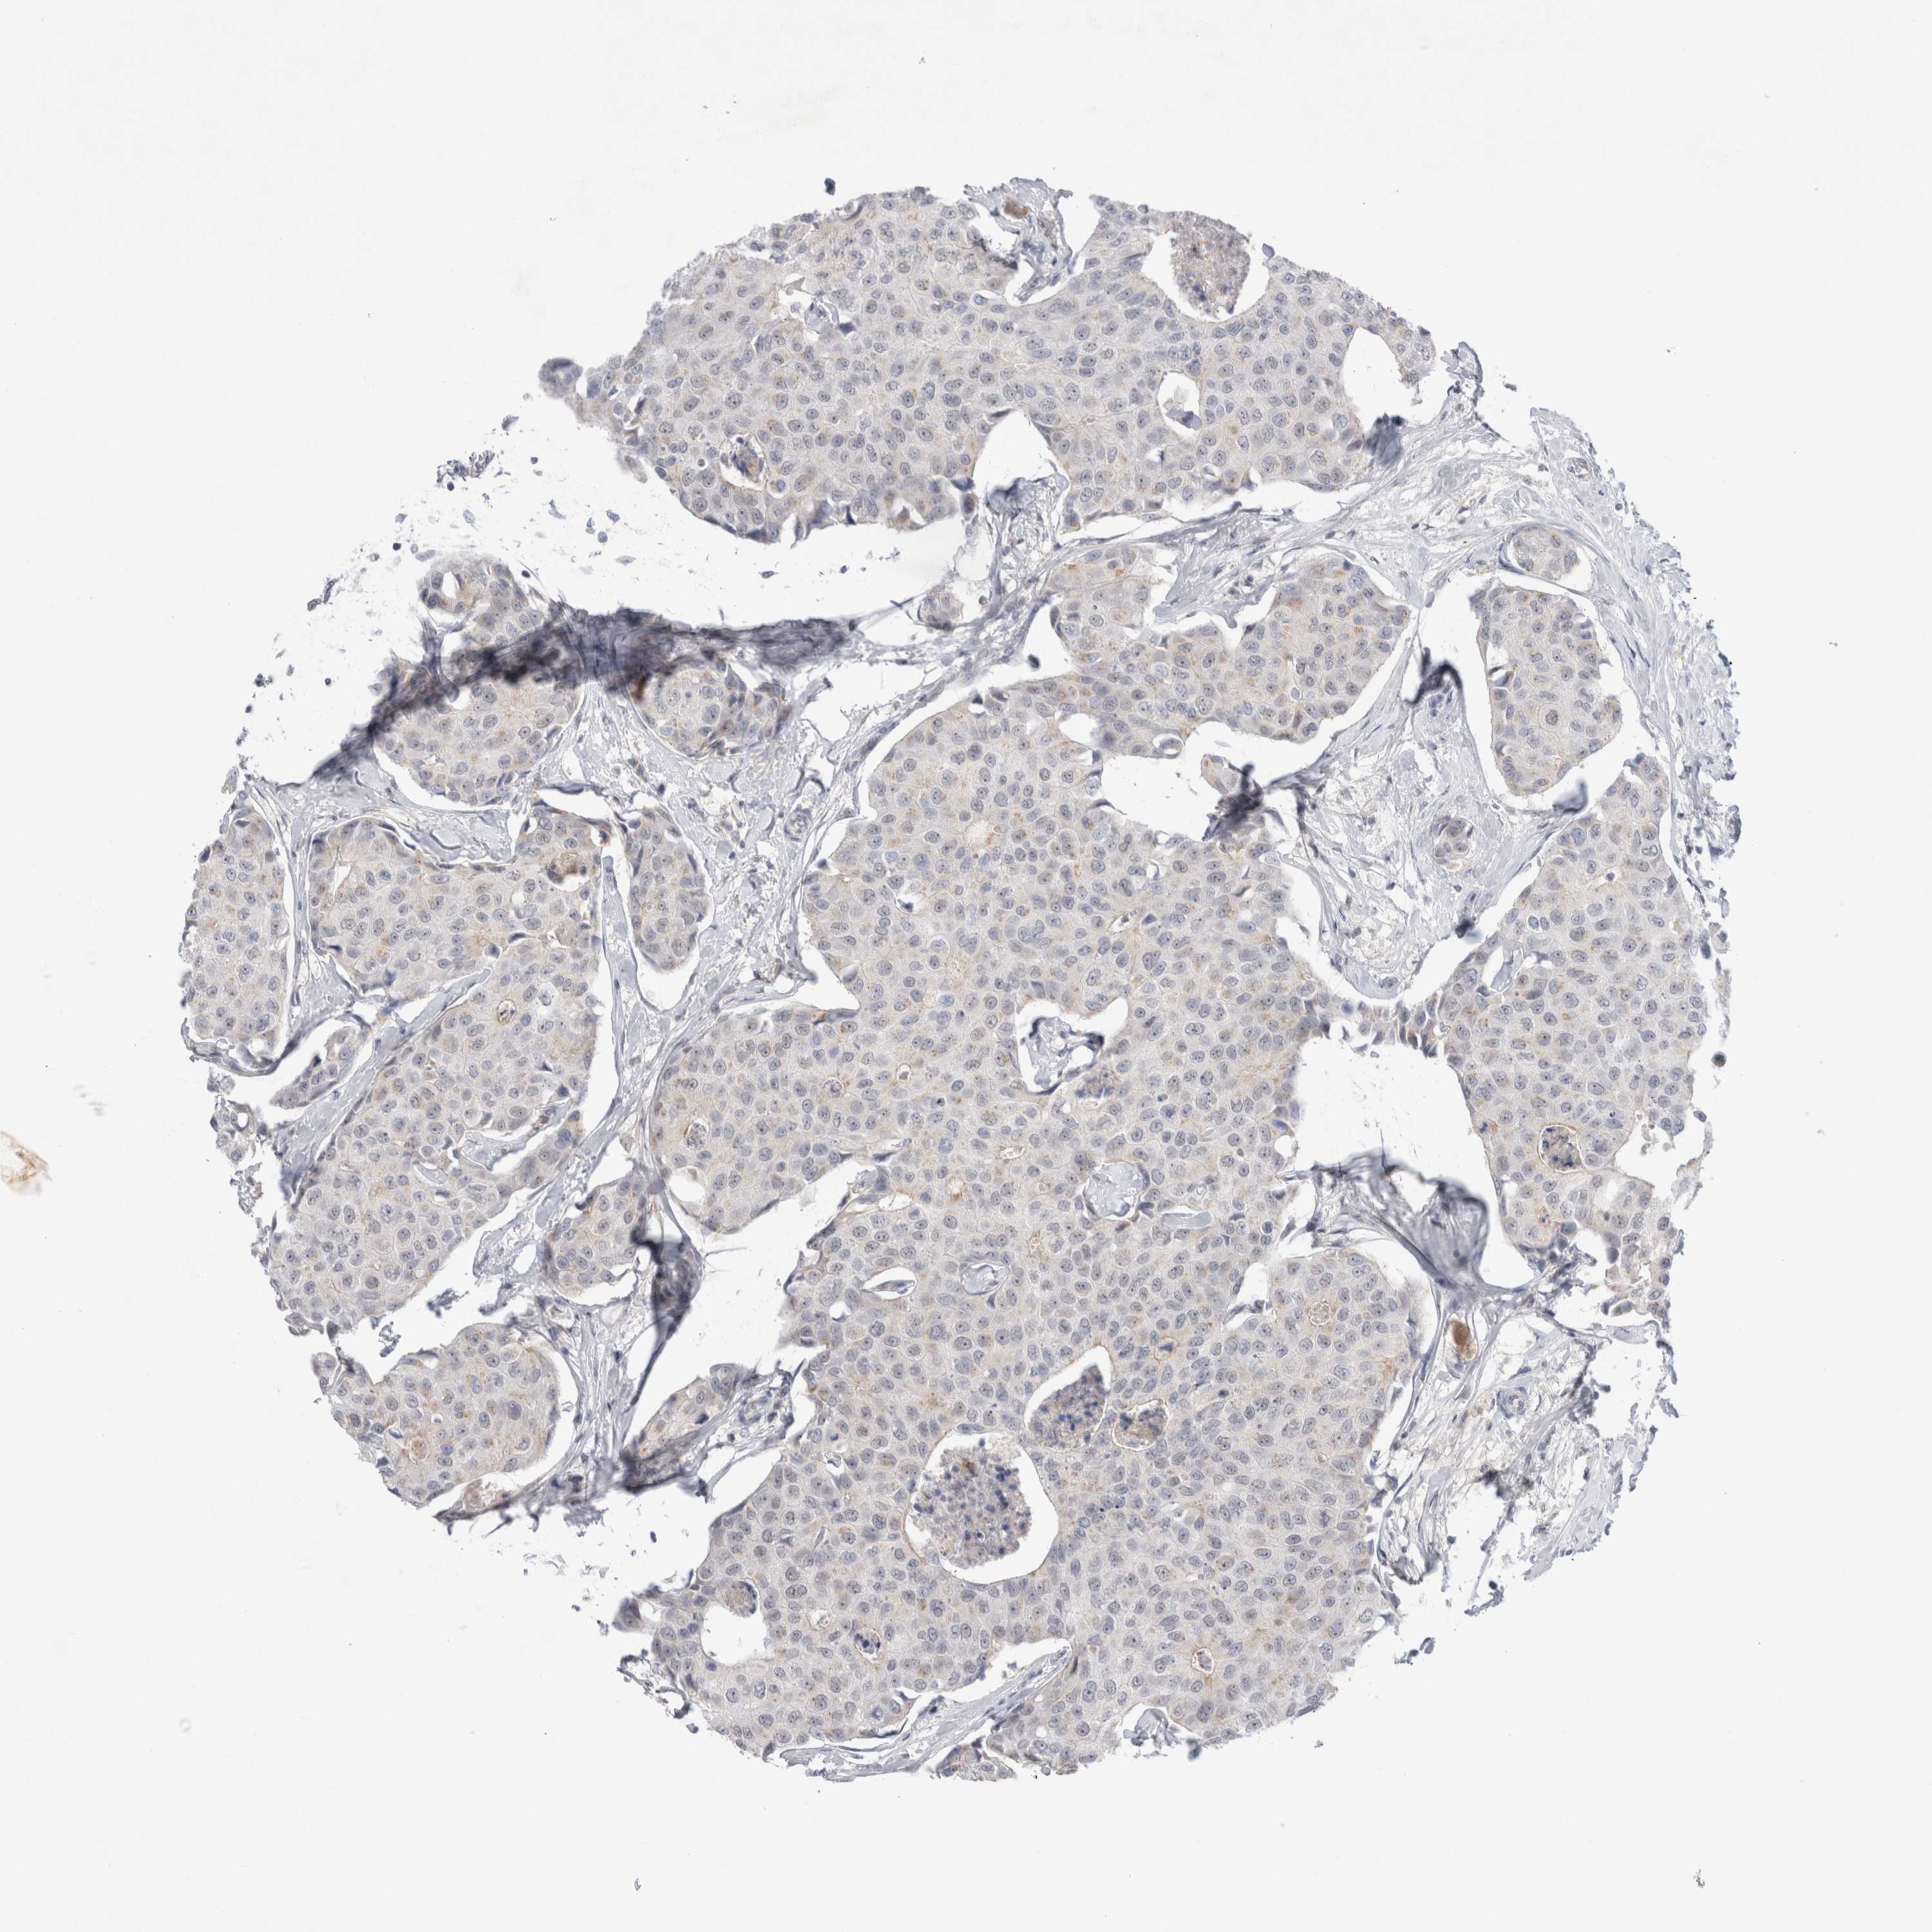

CANCER BREAST CANCER Show tissue menu

BRCA TCGA BRCA VALIDATION PROTEIN EXPRESSION

ANTIBODIES

AND

VALIDATION